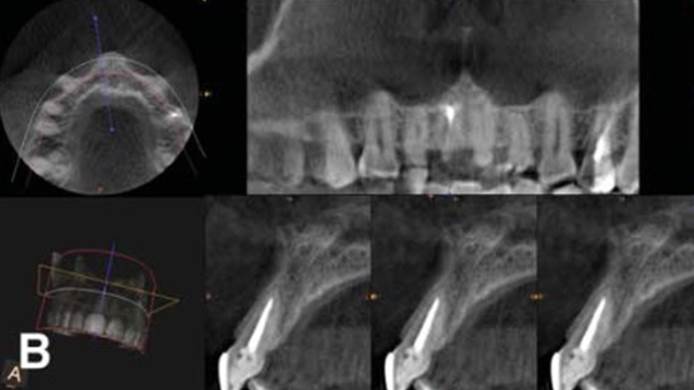

Clinical case: Replacement of fractured central incisor (#11) with immediate implant

& Root Membrane Technique

- Courtesy of Dr. Miltiadis Mitsias, Greece -

Keywords

AnyRidge, Root Membrane Technique, retrospective study, long-term study, immediate implants, bone resorption, bone preservation, Dr. Miltiadis Mitsias,survival, success, maxillary anterior, single replacement

Products:

AnyRidge implant system, Root Membrane kit

Reference

The Root Membrane Technique: A retrospective clinical study with up to 10 years of follow-up./Implant Dent. 2018 Oct;27(5):564-574

https://www.ncbi.nlm.nih.gov/pubmed/30161062